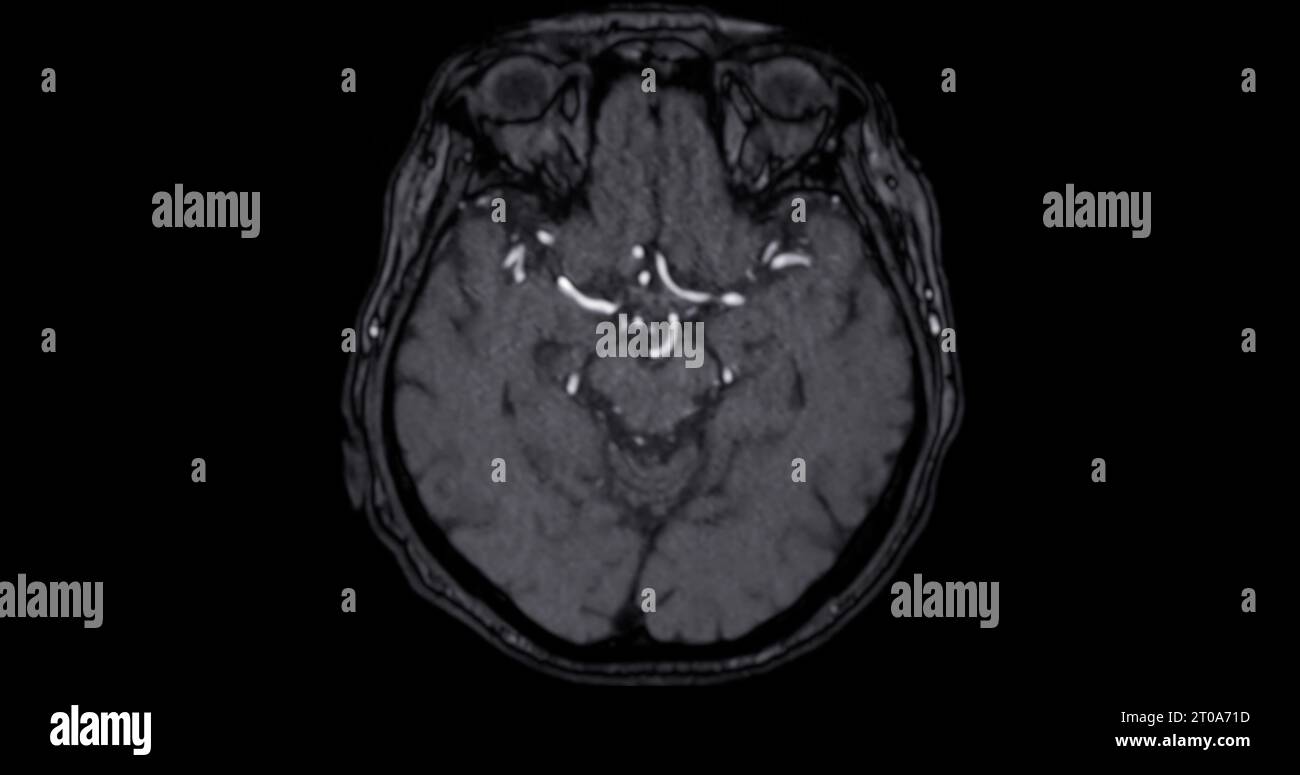

MRI brain axial and sagittal plane with gadolinium contrast for detect What Can Mri Brain Detect Mri is often used to detect brain tumors because it shows the brain more clearly than do other imaging tests. Mra can also be used to detect intracranial (within the brain) aneurysms and vascular malformations (abnormalities of blood vessels within the brain, spinal cord, or other parts of. This information can help guide. A variant called mr angiography (mra) provides.. What Can Mri Brain Detect.

MRI brain axial diffusion image for detect stroke disease and Brain What Can Mri Brain Detect An mri of the brain can be used to evaluate many symptoms which may be caused by abnormalities in the central nervous system. In the case of an ischemic stroke, caused by a blocked blood vessel, an mri can show areas of the brain that are suffering from lack of blood flow. Mra can also be used to detect intracranial. What Can Mri Brain Detect.